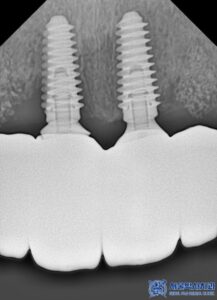

임플란트 보철물과 나사를 연결해 주는

기둥은 기성, 맞춤형 두 가지 방식이 있는데요.

수정구치과 서울박사에서는

기성 어버트먼트가 아닌

맞춤형 지대주를

제작해드리고 있습니다.

✅음식물이 잘 끼지 않아 위생적

기성 지대주는 일정한 형태로 제작되어 있어

환자의 잇몸 형태와 완벽하게

맞지 않는 경우가 많습니다.

반면 맞춤형 지대주는 환자의 구강 구조에

맞게 정밀하게 제작되므로,

잇몸과의 밀착력이 뛰어나

음식물이 끼는 현상을 줄일 수 있습니다.

✅강도와 내구성이 뛰어남

맞춤형 지대주는 개개인의 구강 상태에 맞춰

설계되기 때문에 기성 제품보다 강도와

내구성이 뛰어납니다.

특히 앞니와 같은 부위는 씹는 힘보다는

심미적인 요소가 중요하기 때문에,

강도와 심미성을 모두 고려한

맞춤 제작이 필수적입니다.

✅자연스러운 심미적 효과

맞춤형 지대주는 보철물과의 연결 부위가

매끄럽게 이어져 치아가 보다

자연스럽게 보이도록 도와줍니다.

또한 잇몸 라인도 딱 맞게 제작되어

임플란트 치아가 마치 원래

내 치아처럼 보이는 효과를 줍니다.